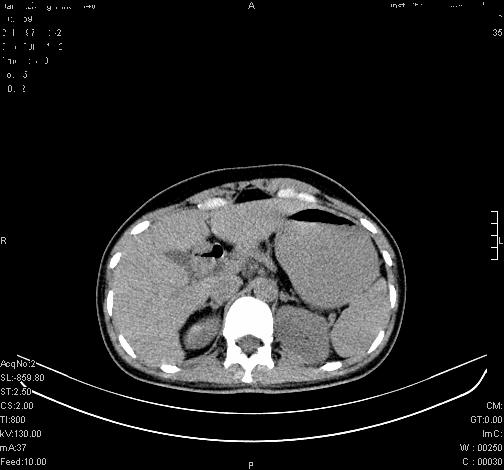

患者为年轻女性,查体发现右侧肾上腺囊性占位。无临床体征。

这么漂亮的图像,一看一目了然。典型的右侧肾上腺囊肿,周围有钙化。感谢搂主!

这么明显的弧形钙化,多考虑包虫病所致的寄生虫性囊肿。

右侧肾上腺囊性密度灶囊壁有钙化。考虑肾上腺囊肿,结核?

右侧肾上腺囊肿,周围有钙化。